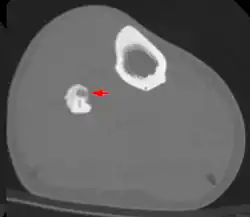

Sie bestehen aus einem stark gefäßversorgten „Kern“ (Nidus), der von einer rundlichen oder spindelförmigen Zone reaktiv wachsenden, verdichteten (sklerotischen) reifen Knochengewebes umgeben ist. Vorzugsweise sind Osteoid-Osteome in Ober- und Unterschenkelknochen lokalisiert. Überschreitet der Nidus eine Größe von 1,5 cm, wird die Veränderung als Osteoblastom bezeichnet.

Die Diagnosestellung erfolgt mittels bildgebender Verfahren: Röntgen, Knochenszintigrafie, CT und MRT (vorzugsweise als dynamische Untersuchung mit Nachweis einer arteriellen Kontrastmittelanreicherung im gut durchbluteten Nidus).[1][2]

Die Therapie besteht in der operativen Entfernung mittels offener Resektion oder perkutaner Stanzbiopsie oder vorzugsweise CT-gesteuerter Radiofrequenztherapie.[3][4] Alternativ kann beim Vorliegen eines Osteoid-Osteoms auch eine symptomatische Behandlung mit Aspirin oder anderen Nichtsteroidalen Antiphlogistika erfolgen,[5] da in der Regel eine Ausheilung der Erkrankung in einem Zeitraum von etwa 2 bis 7 Jahren beobachtet wird.